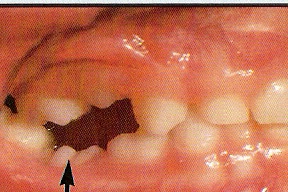

Klinicznie obserwuje się infrapozycję zęba reinkludowanego – obniżenie powierzchni żującej zęba w stosunku do powierzchni zgryzu (skutek miejscowego zahamowania wzrostu kości wyrostka zębodołowego). Stwierdza się (nie w każdym przypadku) metaliczny odgłos opukowy lub utratę mobilności zęba przyczynowego.

Na skutek reinkluzji może dojść do mezjo-dystalnego nachylenia (tipping) powierzchni żujących koron zębów sąsiednich w kierunku zęba przyczynowego i ich niewielkiego zagłębienia. Nachylenie zębów sąsiednich tworzy korzystne warunki do nadmiernej akumulacji płytki nazębnej, stwarza problemy higienizacyjne i przyczynia się do dynamicznego rozwoju próchnicy.

Ciężka reinkluzja mlecznych trzonowców z tippingiem sąsiednich zębów może powodować poważne zaburzenia ortodontyczne (zgryz otwarty boczny, zgryz krzyżowy boczny, przesunięcie linii pośrodkowej, utrata miejsca w łuku zębowym). Ponadto ząb przeciwstawny bez oparcia ma tendencję do suprapozycji (wysuwania się w kierunku zęba zagłębionego).